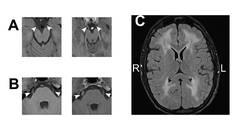

Reversible Cortical Blindness Secondary to Acute Carbon Monoxide Poisoning

Leah Rosen, MS; Gabriella Schmuter, MDLeah Rosen, MS; Gabriella Schmuter, MD - Neuromuscular